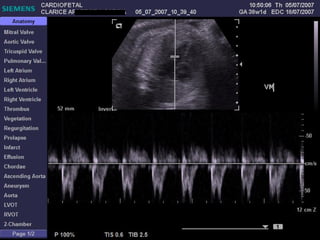

ECOCARDIOGRAFIA FETAL Modo B Modo M Doppler ¿CUANDO? A partir de la sem 12 por vía TV A partir de la sem 18 por vía abdominal Optimo: semana 22

EXAMEN BASICO GENERAL Ubicación Eje Tamaño  Cámaras Pericardio Ritmo VALVULAS AV Apertura y movimiento Inserción AURICULAS Tamaños Flap del foramen oval Septum VENTRICULOS Tamaños Paredes Banda moderadora Tabique

EXAMEN BASICO GENERAL Ubicación Eje Tamaño  Cámaras Pericardio Ritmo

Ritmo